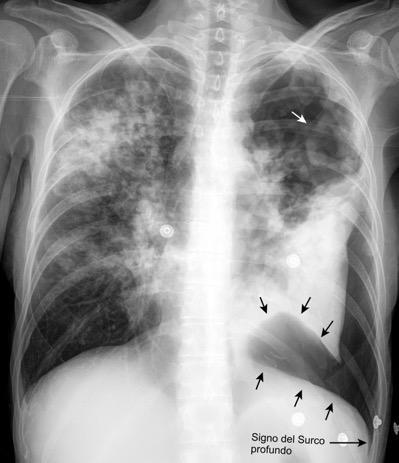

0,4% de casos de trauma. 80% lado izquierdo. Bilateral. 3%

Penetrante..63% 20-59%. Arma de fuego 15-32%. Arma blanca

Trauma cerrado. 37%

Tráfico Caída de gran altura

Aplastamiento toracoabdominal

Furak J et al. Diaphragm and transdiaphragmatic injuries. J Thorac Dis 2019

Accidente de tráfico

Rx: Niveles hidroaéreos en hemitórax izquierdo Desviación mediastínica Ausencia de intestino en abdomen. Configuración en reloj de arena del intestino herniado “Tubo nasogástrico”